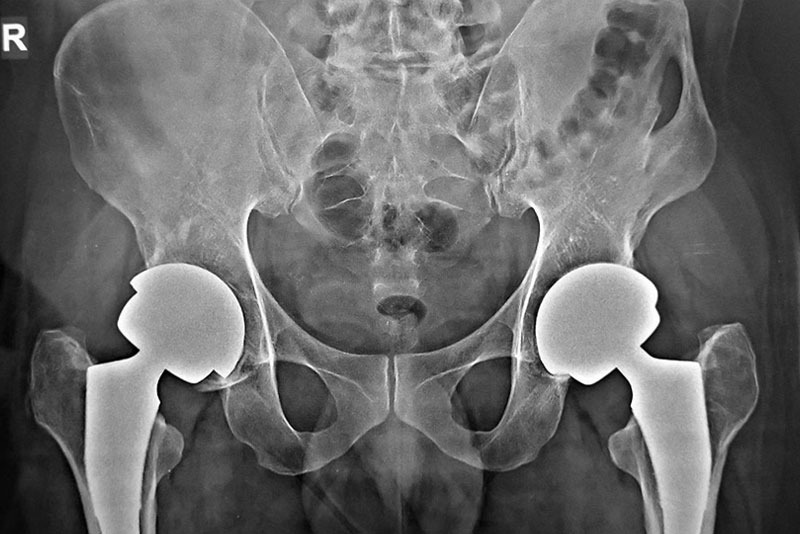

Diagnosis involves physical examination, ultrasound in infants, and imaging studies such as X-rays in older children or adults. Early treatment may include braces or supportive devices to guide proper hip development. When untreated, hip dysplasia can lead to early arthritis and severe joint damage.

In adults with severe joint damage or arthritis, Total Hip Replacement Surgery in Delhi is often recommended. This procedure replaces the damaged joint with artificial implants, relieving pain and restoring movement. Modern surgical techniques, advanced implants, and structured rehabilitation allow patients to regain mobility and improve quality of life.